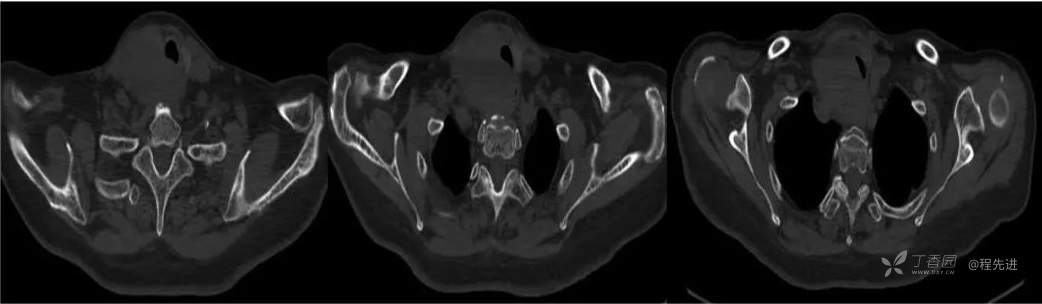

CT

骨窗